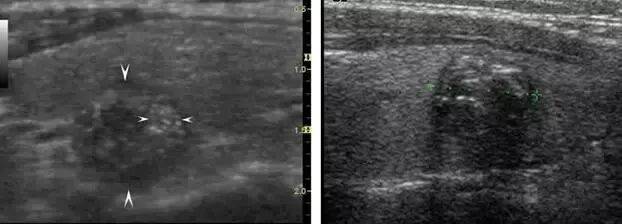

大箭头指向腺体,小箭头指向结节,结节外腺体回声不均

左图大箭头指向结节,小箭头指向微小钙化 。右图虚线上方为颗粒状钙化。

大箭头指向腺体,小箭头指向结节,有的结节伴弧形钙化,结节外腺体回声不均。